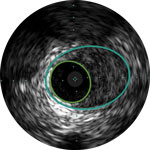

Dr Michael Lichtenberg and Dr Konstantinos Stavroulakis discuss the basics of IVUS image interpretation for PAD intervention. Using case- based examples, they demonstrate the added value of IVUS to assess the architecture and pathology of diseased arteries and how this additional information may influence treatment strategy and improve patient outcomes

Dr Lichtenberg and Dr Stavroulakis discuss the IVUS technical characteristics and the rationale for using IVUS to complement angiography in PAD intervention

Using case based examples, Dr Stavroulakis discusses the four pillars of IVUS, a framework that demonstrates the added value IVUS brings to angiography

Dr Stavroulakis demonstrates the use of IVUS to understand calcium geometry and morphology and how this may influence treatment strategy.

Dr Lichtenberg demonstrates the ability of IVUS to reveal the depth, circumference and free lumen area resulting from dissection and how this may impact treatment strategy.

Dr Stavroulakis discusses how angiography can often underestimate severity of PAD, and how IVUS can accurately measure and quantify percent stenosis and plaque burden.